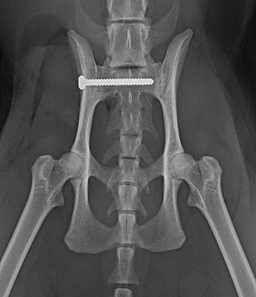

Beispiele aus der Orthopädie

- Frakturoperationen

- Symphysiodese bei Welpen

- Beckenosteotomie (DPO/TPO)